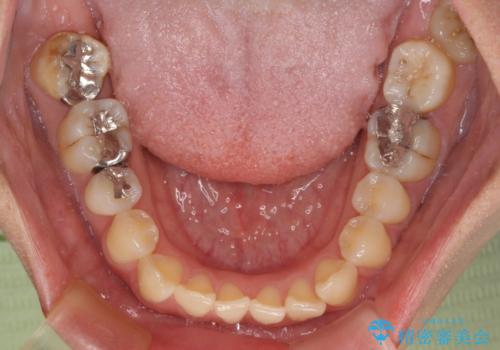

上下前歯のデコボコを気にして来院された患者様です。

ワイヤー矯正でもマウスピース矯正でも可能でしたが、短期間で、自身の手を煩わせることなく治療を行いたいとのことで、ワイヤー装置にて矯正治療を行うこととしました。

舌の突出癖により、治療過程でスペースが多くできましたが、舌のトレーニングを頑張っていただき、1年強で終えることができました。